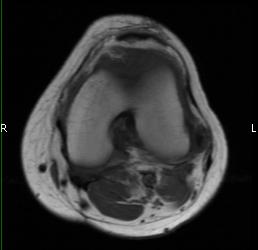

MRI (Fig. 1-10)

- Periarticular or synovial nodular mass with varying degrees of bone erosion.

- Nodular lesion with areas of hemosiderin (low signal on all sequences) and hemorrhage.

- On fat suppress images the tumor is high signal and hemosiderine cannot be seen.

- Joint effusions and bony erosions are well demonstrated. As with CT, contrast enhancement is typical.

Fig. 1-10: Magnetic Resonance of a PVNS of the knee shows a synovial mass with minimal bone erosion of the medial articular plate. On T1W and T2W images shows a tumor with low intensity areas (hemosiderin) and hemorrhage. Joint effusion is well demonstrated. Post contrast images demonstrate an irregular pattern of enhancement.